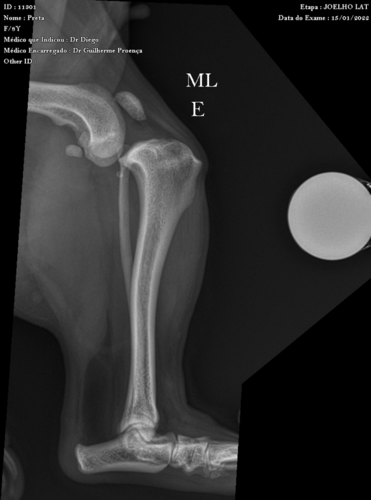

Minha cachorrinha de 9 anos foi descer do sofá (que por sinal era baixo) ao ouvir um latido na rua e acabou escorregando. Infelizmente a pretinha rompeu o ligamento cruzado do joelho esquerdo, em uma queda boba como essa…desde então ela está mancando e não tem firmeza no joelhinho :(

A cirurgia em questão se chama Sutura Fabelo Tibial, uma técnica eficiente na estabilização imediata da articulação de cães, oferecendo recuperação funcional ao reduzir o deslocamento cranial e a rotação interna da tíbia. Você pode saber mais acessando o link da descrição técnica.

-LAUDO:

RAIO X: